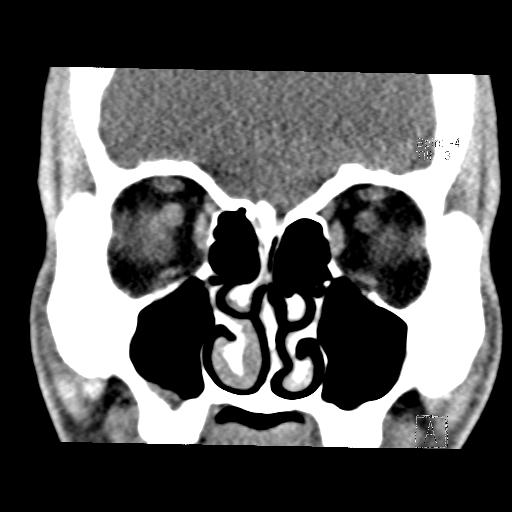

While my right inferior turbinate is the major target here, other slices show the middle turbinates:

I presume that both “turbinate” and the alternate name “nasal concha” refer to the coiled shape here, like a turbine or a conch shell.

Working together the turbinates channel airflow through three primary paths in each nasal passage: below the inferior turbinate, between the inferior and the middle turbinates, and above the middle turbinate.